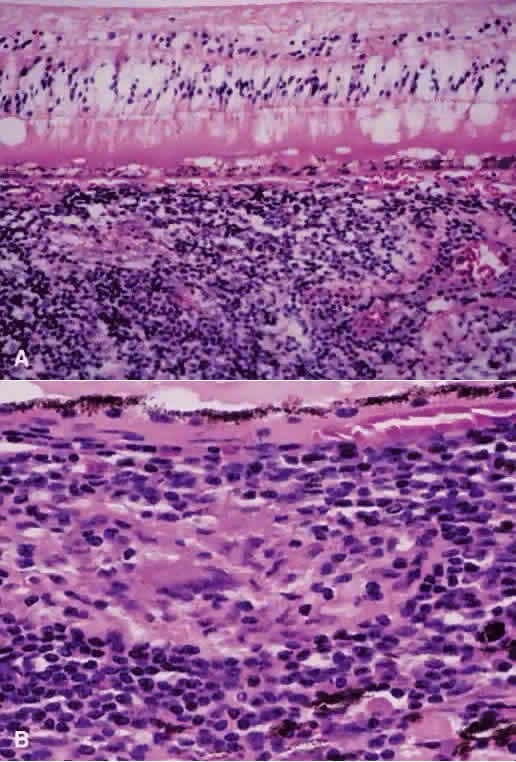

Histopathologic data about Behçet's uveitis come from a few pathologic reports on enucleated, blind, painful eyes with chronic disease.43 Light microscopy usually shows a panuveitis with infiltrating polymorphonuclear leukocytes, lymphocytes, plasma cells, and macrophages (Fig. 7). Immunohistochemical studies have shown a perivascular choroidal infiltration of activated CD4+ , but not CD-8+ , T cells,44,45 as well as focal aggregates of B cells and plasma cells, with increased expression of cell adhesion molecules on vascular endothelial cells.43 These findings imply a mixture of cellular and humoral components in the pathogenesis of Behçet's ocular vasculitis, in which CD4+ cells activate B cells, resulting in enhanced local production of antibodies and immune complex deposition.43 However, the nature of the antigen in the complex is not known.

Fig. 7. Photomicrograph from eye of patient with Behçet's disease showing infiltration of retina with acute and chronic inflammatory cells, especially in the perivascular region (hematoxylin and eosin; × 400). (Photomicrograph courtesy of Professor Hajime Inomata, Kyushu University, Fukuoka, Japan.)